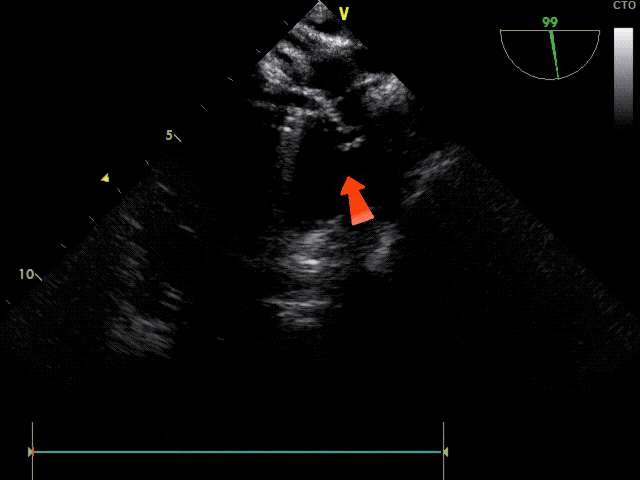

锁定前观察

锁定前观察,确认封堵器骑跨于房间隔两侧,稳固夹持

确认封堵器锁定形态无误